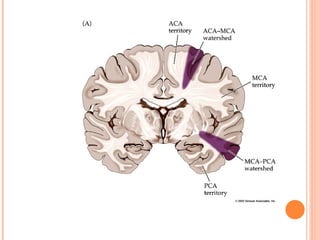

TERRITORIES OF

CEREBRAL ARTERIES

ANTERIOR CEREBRAL ARTERY

AREA SUPPLIED

 Medial part of orbital surface of frontal lobe

[includes olfactory bulb and tract]

 Medial surfaces of frontal and parietal lobes

 Corpus callosum

 A strip on lateral surface

POSTERIOR CEREBRAL

ARTERY

MIDDLE CEREBRAL

AREA SUPPLIED  Medialpart of orbital surface of frontal lobe [includes olfactory bulb and tract]  Medial surfaces of frontal and parietal lobes  Corpus callosum  A strip on lateral surface